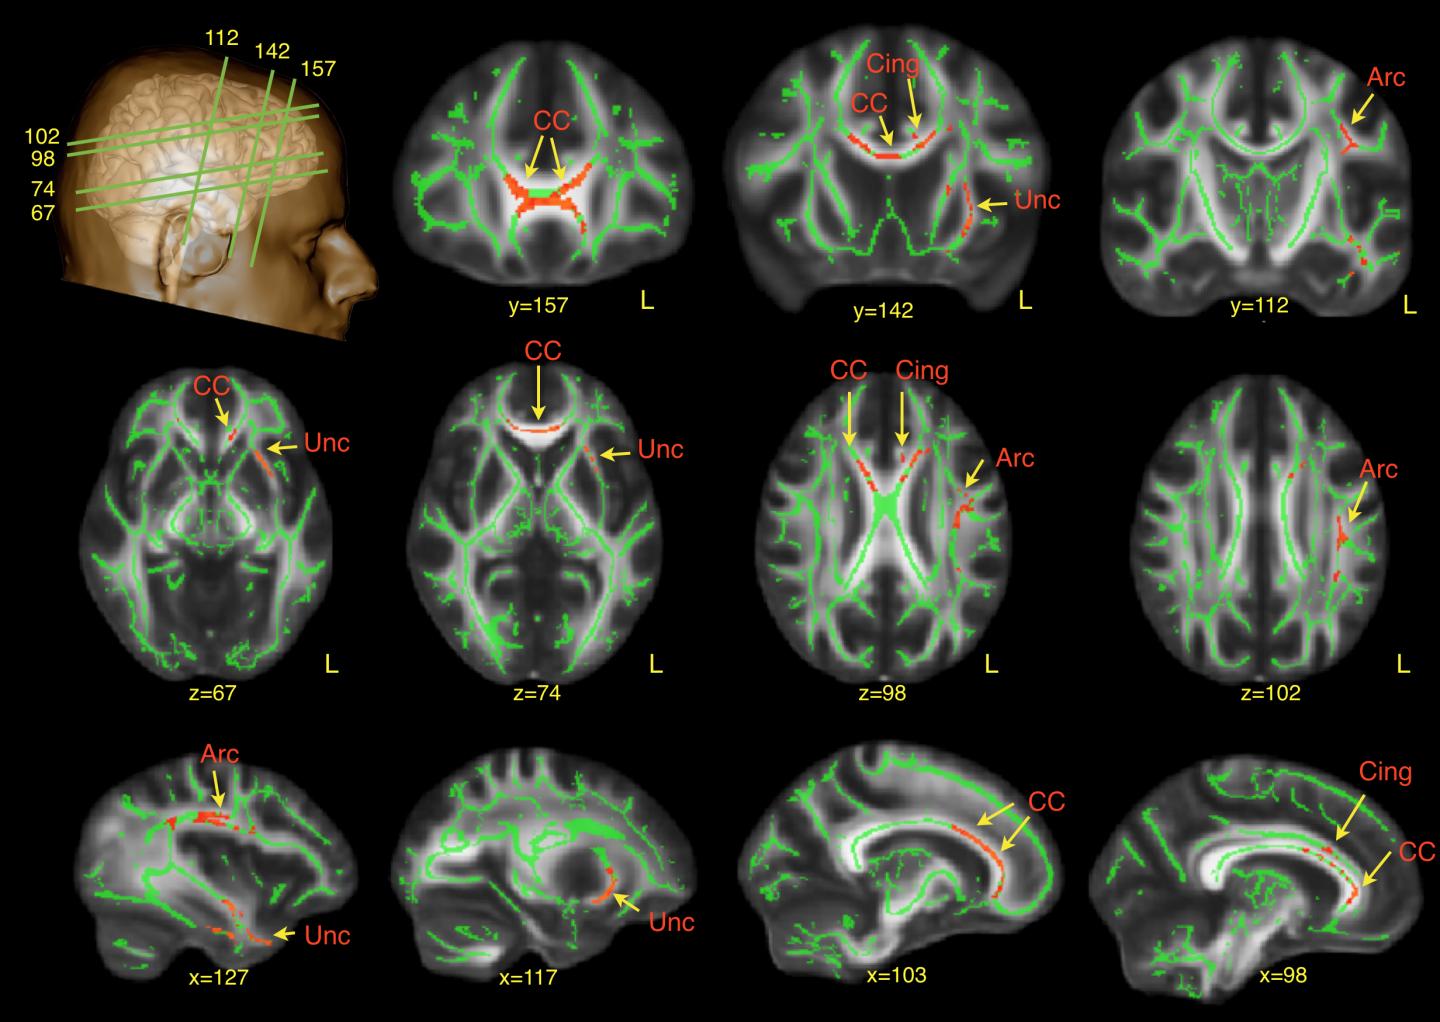

The study, published today in the journal Brain , used a novel brain imaging method to identify altered brain connections in people with ASD. The researchers used Diffusion Tensor Imaging (DTI), a Magnetic Resonance Imaging (MRI) technique, to compare networks of white matter in 61 adults with ASD and 61 controls. White matter consists of large bundles of nerve cells that connect different regions of the brain and enable communication between them.

The scans revealed that men with ASD had differences in brain connections in the frontal lobe, a part of the brain that is crucial to developing language and social interaction skills.

Specifically, these men had altered development of white matter connections in the left side of the brain, the arcuate bundle, which is involved in language. The differences in the arcuate bundle, which connects areas of the brain involved in understanding words and regions related to speech production, were particularly severe in those who had a significant history of 'delayed echolalia'. Delayed echolalia is very common in ASD and manifests in the parrot-like repetition of words or sentences.

ASD was also associated with underdevelopment of white matter in the left uncinate bundle, which plays a significant role in face recognition and emotional processing. This also correlated with observations of 'inappropriate use of facial expression'in childhood.